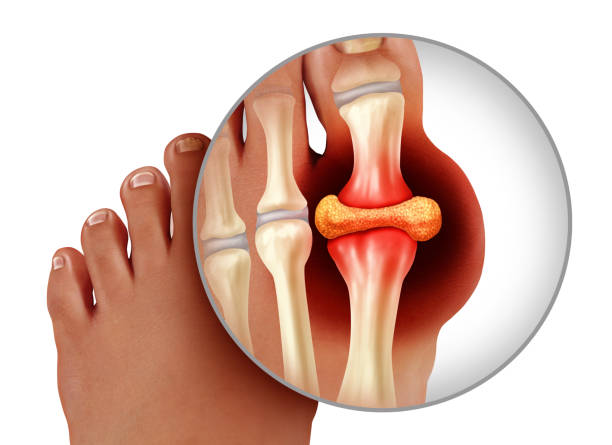

통풍이란 질병은 몸 속 요산이라는 물질이 쌓이면서 그 요산이 우리 몸에서 염증 반응을 일으켜 몸에서 관절염과 심한 통증, 또 콩팥이 망가지는 질환이자 자가 염증질환으로 알려져 있으며 주로 발가락, 발등과 같은 관절에 나타나 통풍이 생긴 경우 다리를 절단하고 싶을 정도로 아주 극심한 통증을 유발하는데 더 무서운 점은 치료시기를 놓치면 말기신부전, 뇌졸중, 심근경색 등 생명을 위협할 수 있는 합병증을 유발합니다.

통풍 증상은 그 시기에 따라 고요산혈증, 급성 통풍성 관절염, 간헐기 통풍 등 3가지 단계로 나눌 수 있으며 전형적 증상은 갑자기 엄지발가락 부위가 조금 뻐끈하다는 느낌으로 시작하며 이 부위가 급격히 붓고 통증이 심해지면 관절 주변 피부가 일어나면 열감이 느껴지고 종국에는 신발을 신을 수 없을 정도로 극심한 통증을 겪게 됩니다.